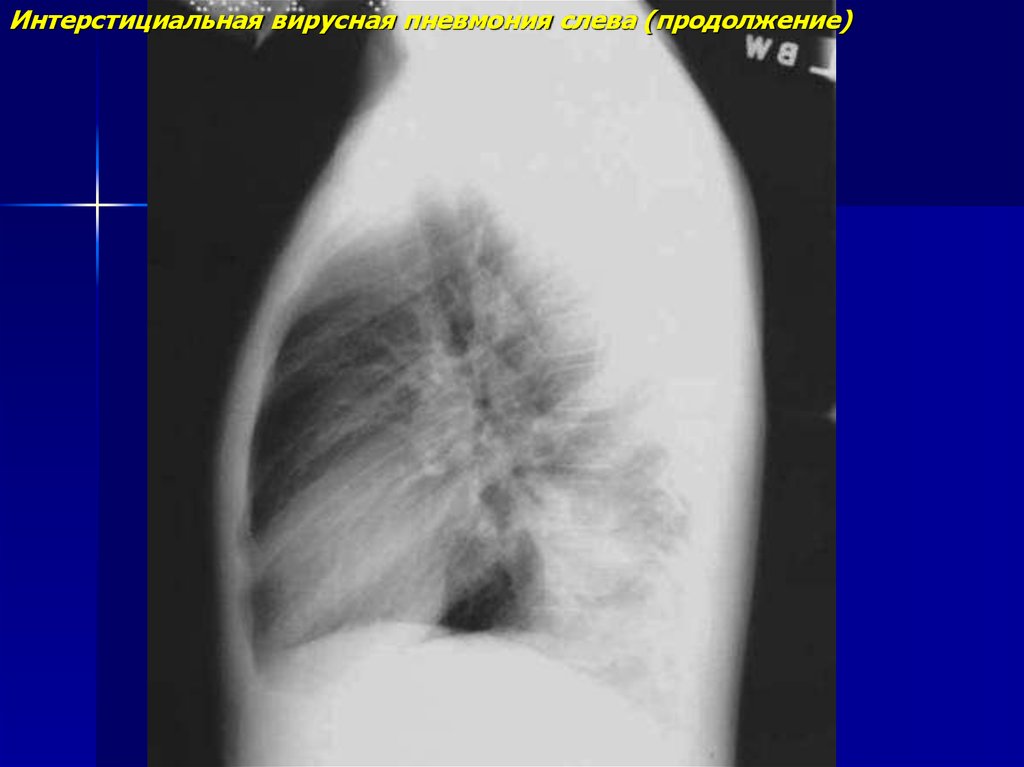

Интерстициальная вирусная пневмония слева (продолжение)

5.